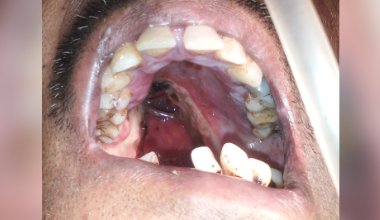

OBTURATOR PROSTHESIS IN POST ONCOLOGICAL MAXILLOFACIAL PATIENTS.

Obturator is a prosthesis used to close a congenital or acquired tissue opening primarily of the hard palate or / and contiguous alveolar structures.Treatment of oral cancer necessitates surgical removal of the affected Maxillofacial hard and soft tissues.

A maxillectomy/ pallectomy prosthesis or obturator restores the surgical defect and aids in the function of speaking, chewing or swallowing. It fills the void left by the surgery and artificially replace lost tissues and teeth.